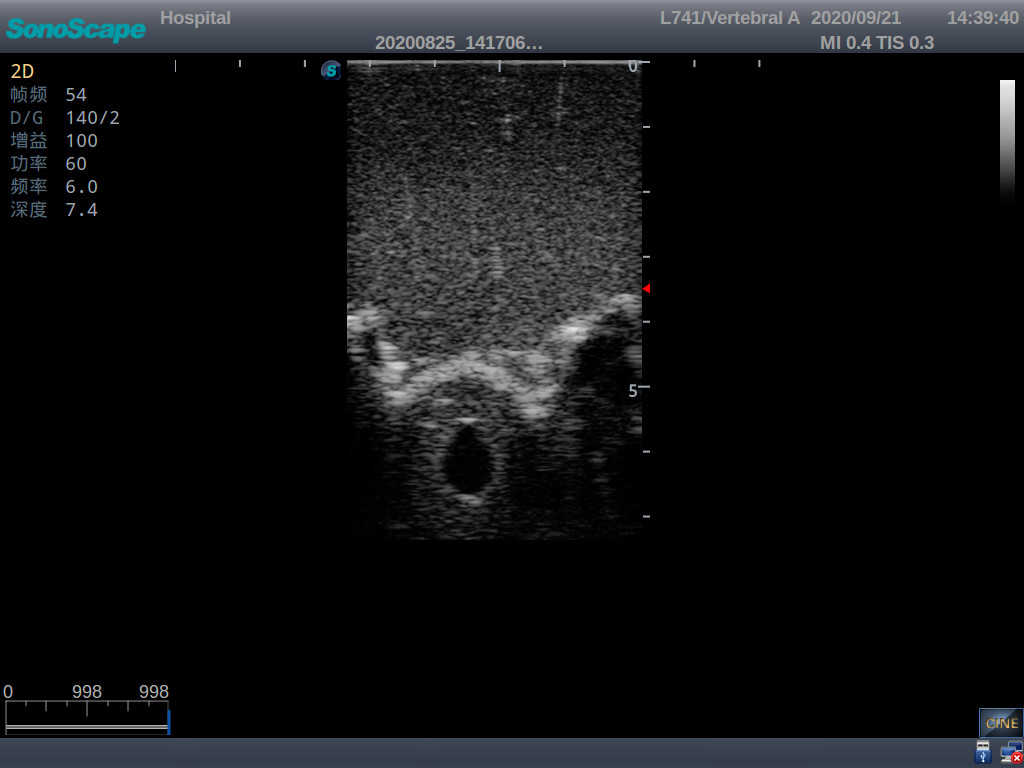

Adult Lumbar Puncture Ultrasound Training Model

Model TYE1549.2

This model is an ideal choice for ultrasound-guided adult lumbar puncture training with true-to-life skin feel and touch, accurate anatomical structures as well as real clinical ultrasound images. Realistic resistance to needle tips and correct landmarks provide excellent hands-on experience.

Accurate anatomical structure of L1-L5 and the vertebral canal

2)  Real clinical ultrasound images

3)  Compatible with various real ultrasound machines

1)   Ultrasound-guided lumbar puncture practice